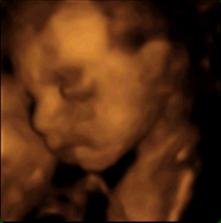

tak sme sa prehupli do tretieho trimestra - a čakame malu copaňu. Tešime sa na ňu.